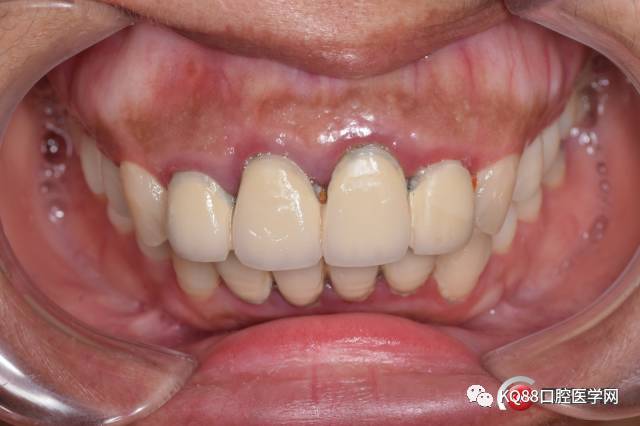

初诊检查:前牙烤瓷连冠修复,牙龈肿胀, A2根尖瘘管,自诉已经五年了。

初诊照片:

根管治疗完善后,过了一个月患者瘘管没有再复发就修复了,然后以为就没有然后了,结果今天3月30日患者来突然说瘘管又有点溢脓了,之前跟她沟通过再有溢脓就要行根尖手术: